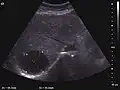

US examination is required to detect liver metastases in patients with oncologic history. In addition, the method can incidentally detect metastases in asymptomatic patients. Early identification (small sizes, small number) is important to establish an optimal course of treatment which can be complex (chemotherapy, radiofrequency ablation, surgical resection) but welcomed. In addition, discrimination of synchronous lesions that have a different nature is also important knowing that up to 25–50% of liver lesions less than 2 cm detected in cancer patients may be benign . US sensitivity for metastases detection varies depending on the examiner's experience and the equipment used and ranges between 40 and 80% . Sensitivity is conditioned by the size and acoustic impedance of the nodules. For a lesion diameter below 10 mm US accuracy is greatly reduced, reaching approx. 20%. Other elements contributing to lower US performance are: excessive obesity, fatty liver disease, hypomobility of the diaphragm, and certain patterns of hyperechoic or isoechoic metastases that can be overlooked or can mimic benign conditions. Conventional US appearance of metastases is uncharacteristic, consisting of circumscribed lesions, with clear, imprecise or "halo" delineation, with homogeneous or heterogeneous echo pattern. They can be single (often liver metastases from colonic neoplasm) or multiple. Echogenity is variable. When increased, they can compress the bile ducts (which may be dilated) and the liver vessels. Liver involvement can be segmental, lobar or generalized. In this situation a pronounced hepatomegaly occurs. Generally, metastases have non-characteristic Doppler vascular pattern, with few exceptions (carcinoid metastases). Cyst-adenocarcinoma metastases due to semifluid content may have a transonic appearance. When increasing, they can result in central necrosis. CEUS examination is a real breakthrough for detection and characterization of liver metastases.

Increased performance is based on identifying specific vascular patterns during the arterial phase and seeing metastases in contrast to normal liver parenchyma during the sinusoidal phase. CEUS increased accuracy is due to the different behavior of normal liver parenchyma (captures CA in Kuppfer cells) against tumor parenchyma (does not contain Kuppfer cells, therefore CEUS appearance is hypoechoic). To this adds the particularities of intratumoral circulation represented by a reduced arterial bed compared to that of the surrounding normal liver and the absence of the portal vessels . In terms of vascularity, metastases can be hypovascular (in gastric, colonic, pancreatic or ovarian adenocarcinomas) with hypoechoic pattern during arterial phase, and similar during portal venous and late phases, respectively hypervascular (neuroendocrine tumors, malignant melanoma, sarcomas, renal, breast or thyroid tumors) with hyperechoic appearance during arterial phase, with washout during the portal venous phase and hypoechoic pattern 30 seconds after injection.